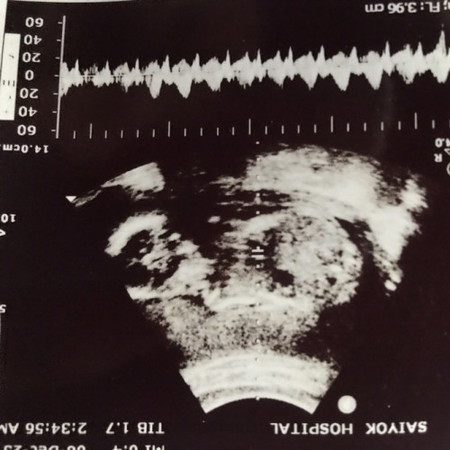

น้อง22วีคเเม่ๆคิดว่าผู้หญิงรึผู้ชายกันคะ

รูปที่ทางโรงบาลปลิ้นให้คะไม่มีเวลาไปซาวที่คลินิกเลย

ไม่สามารถบอกได้ค่ะเพราะในรูปไม่ใช่ตรงส่วนขาค่ะ